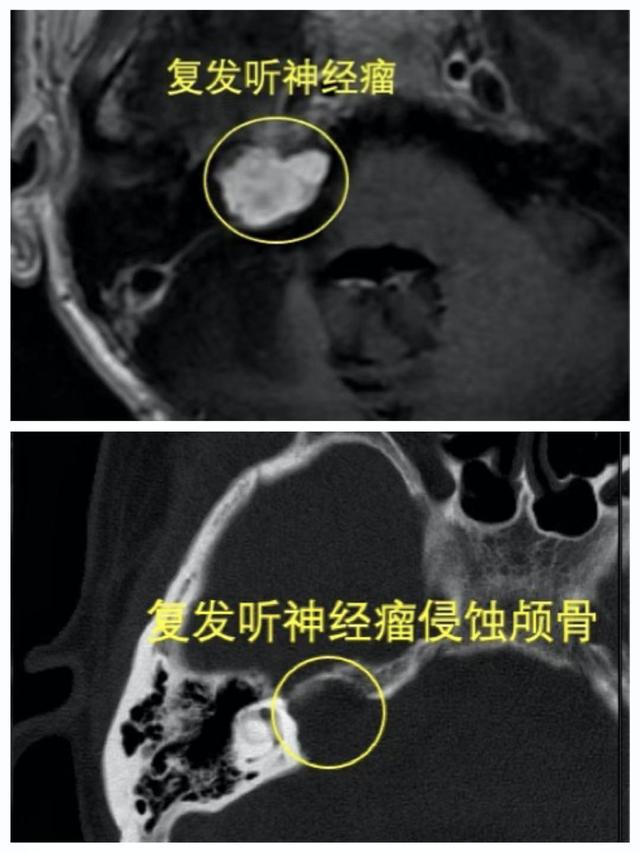

完善检查后 , 杜医生发现 , 这次和上次不同 , 复发的肿瘤严重侵袭骨质 , 相当于“啃”进了骨头里 , 肿瘤的位置在颅底 , 越长越大 , 手术全切可能性将越来越小 , 治疗上越来越被动 。 而像这样的良性肿瘤 , 如果切除完全 , 是可以治愈的 , 如果有残留 , 可能还会复发长大 。 所以 , 手术的目标就是彻底切除 。文章插图